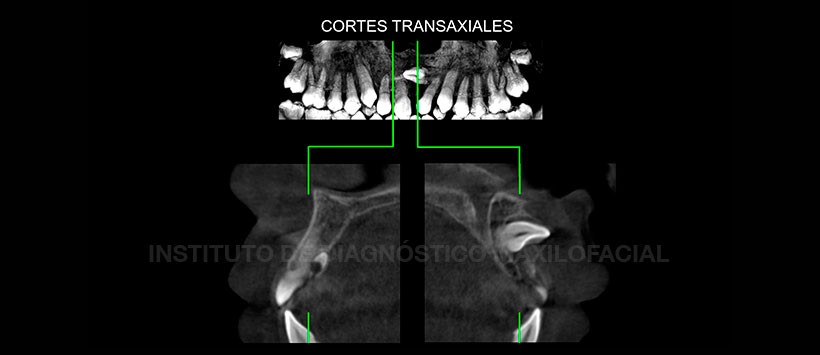

A la evaluación de la tomografía volumétrica de haz cónico, se evidencio en la reformación panorámica la presencia de dicho folículo supernumeraria si como la presencia de la pieza 21. (Figura 2). En la reconstrucción multiplanar (axial, frontal y sagital) y en los cortes transaxiales se evidencio la posición exacta de la pieza 21 y del folículo supernumerario. (Figura 3 y Figura 4). Así como la ausencia de algún tipo de repercusión en relación a las estructuras dentarias y oseas adyacentes.